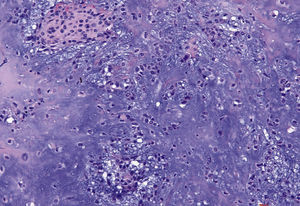

La imagen histológica muestra una proliferación epitelial marcada con crestas epidérmicas ensanchadas y papilomatosis que penetran profun-damente en el tejido conectivo. En la superficie se observan una tendencia evidente a la queratinización y una coilocitosis (tinción de HE, 10 aumentos).

Desde el punto de vista histológico destaca la formación de prolongaciones digitiformes cuyos extremos aparecen queratinizados. La estratificación epitelial está conservada y, en ocasiones, pueden aparecer mitosis. Las atipias epiteliales son raras. Los VPH se pueden identificar con métodos inmunocitoquímicos o mediante la técnica de hibridación in situ8.